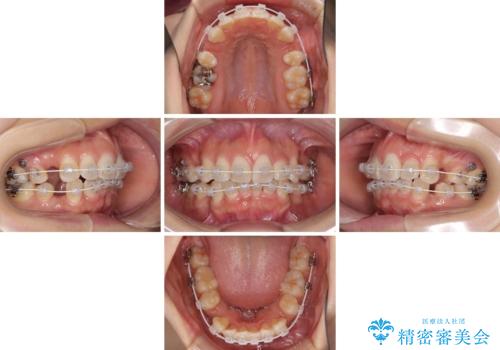

スッキリとした口元へ 出っ歯の抜歯矯正

- 上下の出っ歯を気にして来院された患者様です。

口元を積極的に引っ込めるために、上下左右の第一小臼歯を4本抜歯することとしました。

下顎の正中を上顎に合わせる処置が難航し、期間が長引きました。

最終的には上下の正中も合い、横顔の印象が変わるほどスッキリとした口元となりました。